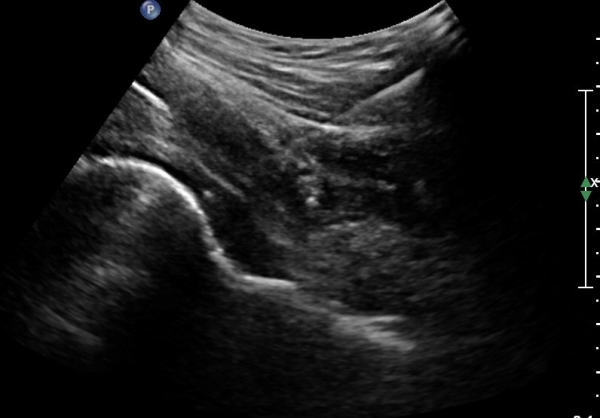

[¾ûµ¢ÀÌ] °í°üÀý Ãæµ¹ÁõÈıº¿¡ÀÇÇÑ È°¾×¸·¿° ÁÖ»çÄ¡·á

ÃÊÀ½ÆÄ °Ë»ç